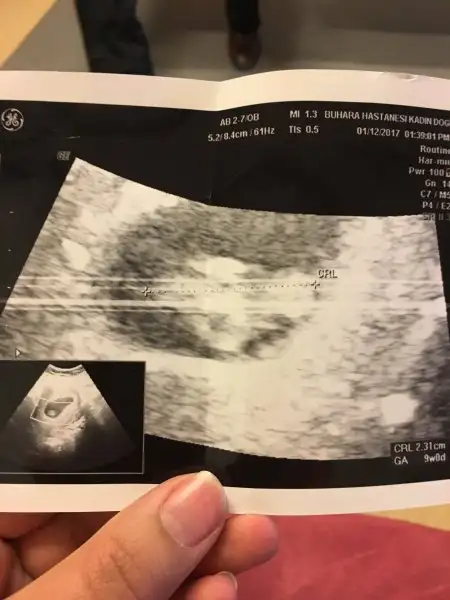

Kızlarr nerdesiniz cevap yok muEki Görüntüle 1939127 Eki Görüntüle 1939128 Kızlar bana da bakar mısınız karından ultrason ve üstteki 9 hafta alttaki 7 haftalık